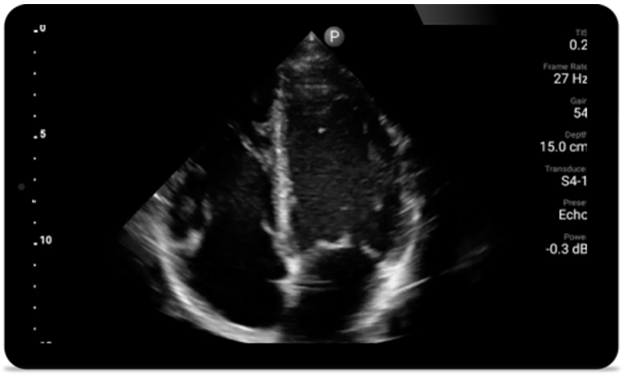

Every second counts

in cardiac care

Heart attack patients need immediate care.

Lumify's cardiac presets can help patients get

diagnosed faster to improve their outcomes.

Lumify S4-1 broadband phased array transducer

• 4 to 1 MHz extended operating frequency range

• 2D, color Doppler, M-mode, advanced XRES and multivariate harmonic imaging

• High-resolution imaging for abdominal and cardiac applications: Cardiac, OB/GYN, Lung, Abdomen and FAST imaging preset optimizations Lumify aids life-saving technology in prehospital setting